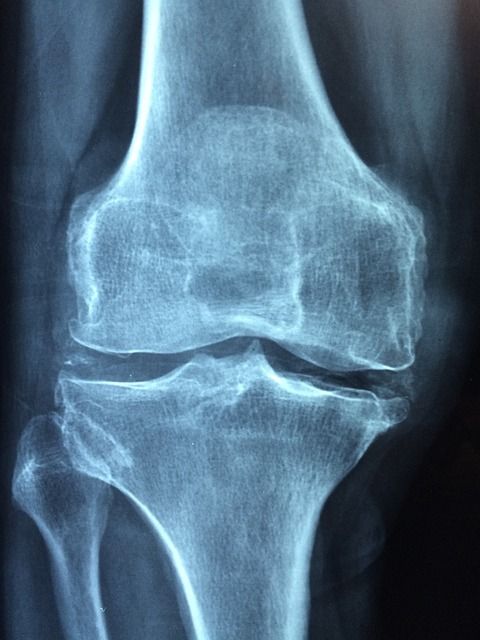

다음으로 질환 조건입니다. 일반적인 무릎 통증이 아닌, 건강보험급여 ‘인공관절치환술(슬관절)’ 인정기준에 해당되는 진단을 받아야 합니다. 다시 말해, 단순한 통증이나 타박상으로는 안 되고, 정형외과에서 ‘퇴행성 관절염’, ‘심한 무릎연골 마모’ 등으로 인해 인공관절 수술이 필요하다는 소견이 나와야 하는 거죠. 이 소견은 반드시 의사의 진단서 또는 소견서로 증명돼야 하며, 수술 예정 병원에서 발급받을 수 있습니다.